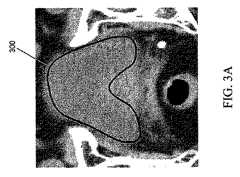

図3A及び3Bは、本発明の実施態様に従い、それぞれ、熟練者が作成した膀胱と前立腺の境界を描写する一対の分節化したCT画像である。図3Aを参照すると、境界300は、例えば、画像におけるピクセル強度の目視検査により医師が決定したヒト男性の膀胱の境界に対応することができる。同様に、図3Bにおいて、境界302は、画像におけるピクセル強度パターンに基づくヒト男性の前立腺の境界である。図3A及び3Bに描写したマニュアル2Dセグメンテーションは、3D領域を提供することができるが、この3D領域に、モデルが当てはめられ、及び更に、解剖学的形態の形態上で、及び対象物に関連した画像情報上で、確率分布を学習する過程でさらに用いられることができる;あるいはそれは標的又はゴールを表すことができて、この標的又はゴールは、ゆっくりした煩雑なマニュアル法で為し遂げることができるが、同様に(又はより正確でさえあるが)自動化した画像処理を用いて;及び本明細書に記載する統計的対象物モデリング法を用いて;為し遂げることができるものである。従って本明細書に記載した、プランニング及び介入がガイドする解剖学的構造のデジタル画像を分節化するための方法の精度の指標としては、画像フィッティング(当てはめ)解析、又は図3A及び図3Bに示すような、熟練者が作成したマニュアルセグメンテーションとの比較が含まれる。 FIGS. 3A and 3B are a pair of segmented CT images depicting the bladder and prostate boundary, respectively, created by an expert according to an embodiment of the present invention. Referring to FIG. 3A, the